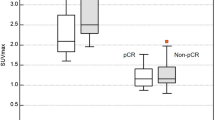

This prospective study included 29 women with histologically proven breast cancer on needle biopsy between July 2016 and July 2019 (age: mean 55 years; range 35–78). Patients underwent WBPET followed by ring-type dbPET and DCE-MRI pre- and post-NAC for preoperative evaluation. pCR was defined as an invasive tumor that disappeared in the breast. Standardized uptake values corrected for lean body mass (SULpeak) were calculated for dbPET and WBPET scans. Maximum tumor length was measured in DCE-MRI images.

Reduction rates were calculated for quantitative evaluation. Two radiologists independently evaluated the qualitative findings. Reduction rates and qualitative findings were compared between the pCR (n = 7) and non-pCR (n = 22) groups for each modality. Differences in quantitative and qualitative data between the two groups were analyzed statistically.

Significant differences were observed in the reduction rates of dbPET and DCE-MRI (P = 0.01 and 0.03, respectively) between the two groups. Univariate and multiple logistic regression analyses revealed that SULpeak reduction rates in WBPET and dbPET (P = 0.02 and P = 0.01, respectively) and in dbPET (odds ratio, 16.00; 95% CI 1.57–162.10; P = 0.01) were significant indicators associated with pCR, respectively. No between-group differences were observed in qualitative findings in the three modalities.

SULpeak reduction rate of dbPET > 82% was an independent indicator associated with pCR after NAC in breast cancer.